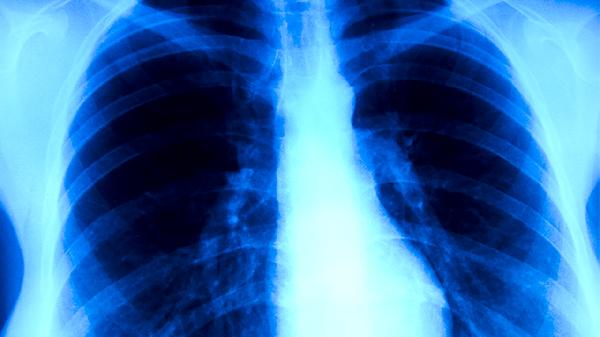

成人患肺结核的症状主要有咳嗽、咳痰、咯血、胸痛、发热等。肺结核是由结核分枝杆菌感染引起的慢性传染病,主要通过呼吸道传播,建议患者及时就医,在医生指导下进行规范治疗。